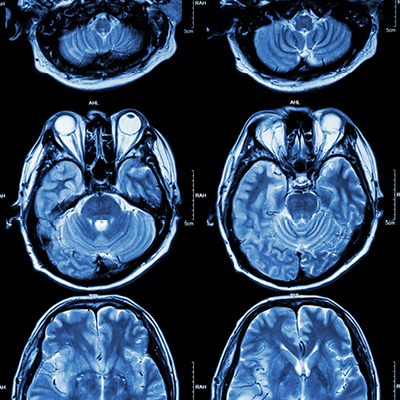

According to the CDC, someone in the US has a stroke every 40 seconds. Those patients who receive emergency care greatly increase their rate of survival and shorten recovery time. A stroke occurs when blood supply is reduced or cut off from the brain, and that root cause is sometimes due to a blood clot.

When a patient comes in and is diagnosed with a stroke, medications can be administered intravenously to break up and restore blood flow back to the brain. However, this medication is only successful around 25 percent of the time when used on large blockages. In these cases, recent advances in technology have opened the door to another treatment option.

If the blockage is not removed quickly, the lack of oxygen to the brain can cause permanent damage to healthy brain cells and lead weakness, paralysis or other permanent disability.